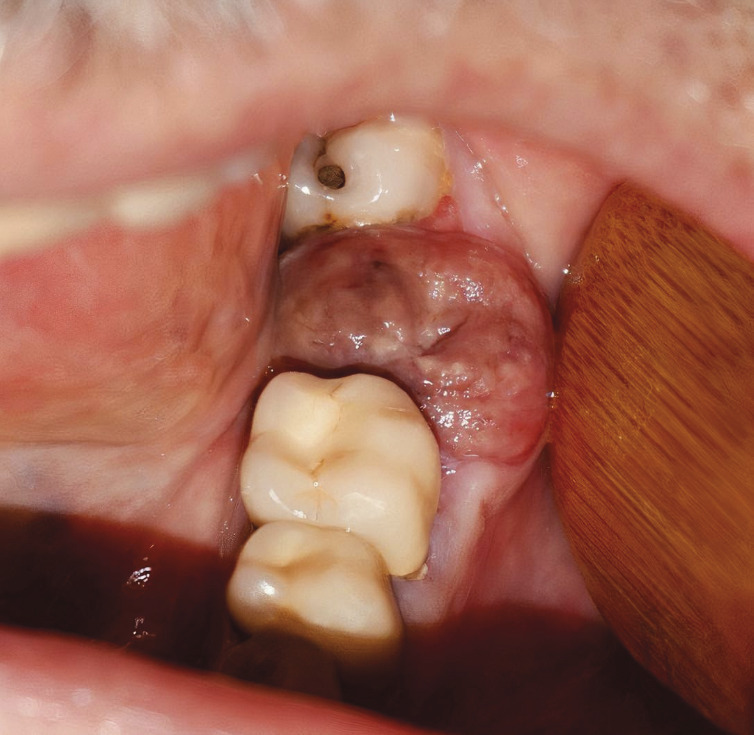

Ce patient de 60 ans consultait pour une lésion gingivale apparue il y a 1 semaine au niveau de l’alvéole de la 2e molaire mandibulaire gauche (37) extraite 1 mois auparavant. L’anamnèse notait un lupus traité par prednisone et hydroxychloroquine, une ostéoporose traitée par acide alendronique arrêté depuis 4 ans et une thrombocytopénie non étiquetée, à 100 000 plaquettes, connue depuis plusieurs années, sans altération de l’état général ni intoxication alcoolo-tabagique. À l’examen clinique endo-buccal (v. figure ), on notait une lésion muqueuse centrée sur l’alvéole d’avulsion de 37, bourgeonnante, sessile, saignant au contact, avec une muqueuse de recouvrement brunâtre et inhomogène ; pas d’adénopathie cervicale ni de lésion osseuse sur la radiographie panoramique. Le diagnostic évoqué était celui de botryomycome (lésion inflammatoire bénigne). L’analyse anatomopathologique de la biopsie-exérèse montrait un chorion infiltré par une prolifération en nappes de grandes cellules basophiles aux noyaux volumineux ainsi que de nombreuses mitoses et corps apoptotiques en aspect de « ciel étoilé » concluant à la localisation d’un lymphome plasmoblastique positif au virus d’Epstein-Barr. Le patient était alors adressé en hématologie pour la suite de prise en charge.